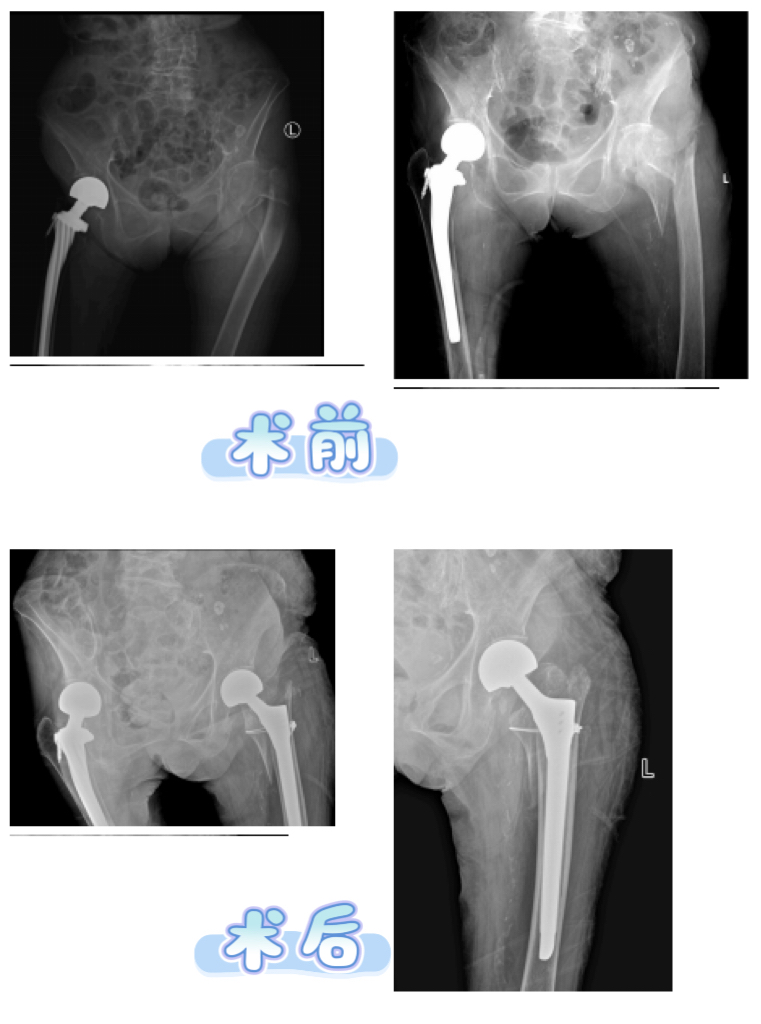

在全身状况逐步改善、各项指标趋于平稳后,手术时机终于成熟。在麻醉科王仿主任团队的严密护航下,骨关节综合科李辉主任团队成功为张奶奶实施右侧髋关节置换术,术后患者安全返回心血管疾病诊疗中心继续治疗。